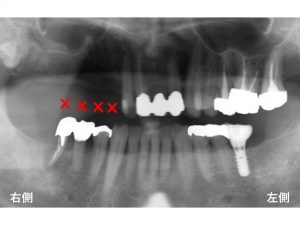

そこで今回は、上顎の右側一番奥歯は、治療の対象とはしない治療計画を立てました。

つまり、上顎右側は、

5歯欠損としてではなく、

4歯欠損のみを治療対象として考えました。

以下の4歯欠損が治療対象です。